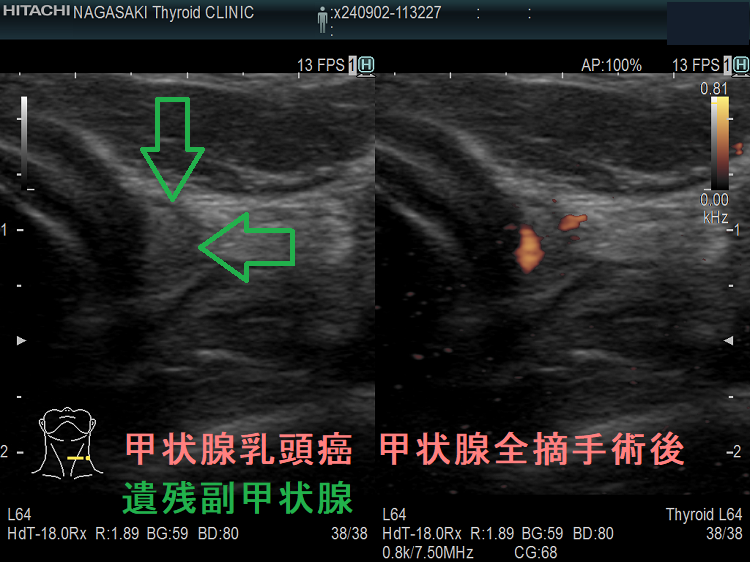

- 甲状腺摘術後、TSH 抑制療法;バセドウ病/甲状腺腫瘍で甲状腺切除と同時に副甲状腺も取ってしまった場合、取らずに温存した場合でも副甲状腺への血管を傷つけた場合

- 甲状腺全摘術時、副甲状腺も1-4腺を同時切除、あるいは切除しなくても栄養血管を損傷

- 術後副甲状腺機能低下症による低カルシウム血症;術直後のみならず、10年~30年以上して著明な低カルシウム血症で発症する事もある(日腎会誌 2012;54(1):40-47.)(J Clin Diagn Res. 2017 Feb; 11(2): OD07–OD09.)。